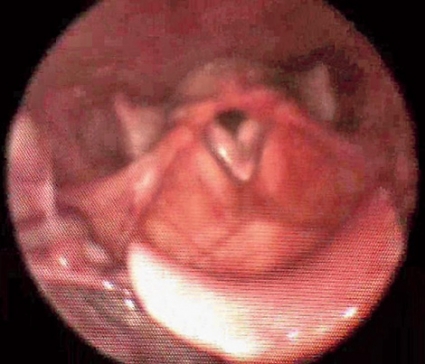

I vårt material hade många patienter supraglottisk obstruktion, och dessa kan i vissa fall opereras med framgång. Vårt material växer stadigt, och vi ser olika bilder av supraglottisk kollaps (Figur 1 och 2), ibland glottisk adduktion (Figur 3) eller en kombination av dessa (Tabell I). I de fall där man påvisar glottisk adduktion (EI-VCD) kan operation inte rekommenderas, och det är ovisst om vi i framtiden kan erbjuda dessa patienter någon hjälp. Andningsteknik i samråd med logoped och/eller sjukgymnast [11] är en möjlig väg att gå, men effekten är svår att utvärdera.

Vi vill dock i detta sammanhang påtala hur viktig nivådiagnostiken är, eftersom det endast är patienter med supraglottisk obstruktion som kan ha nytta av operation.